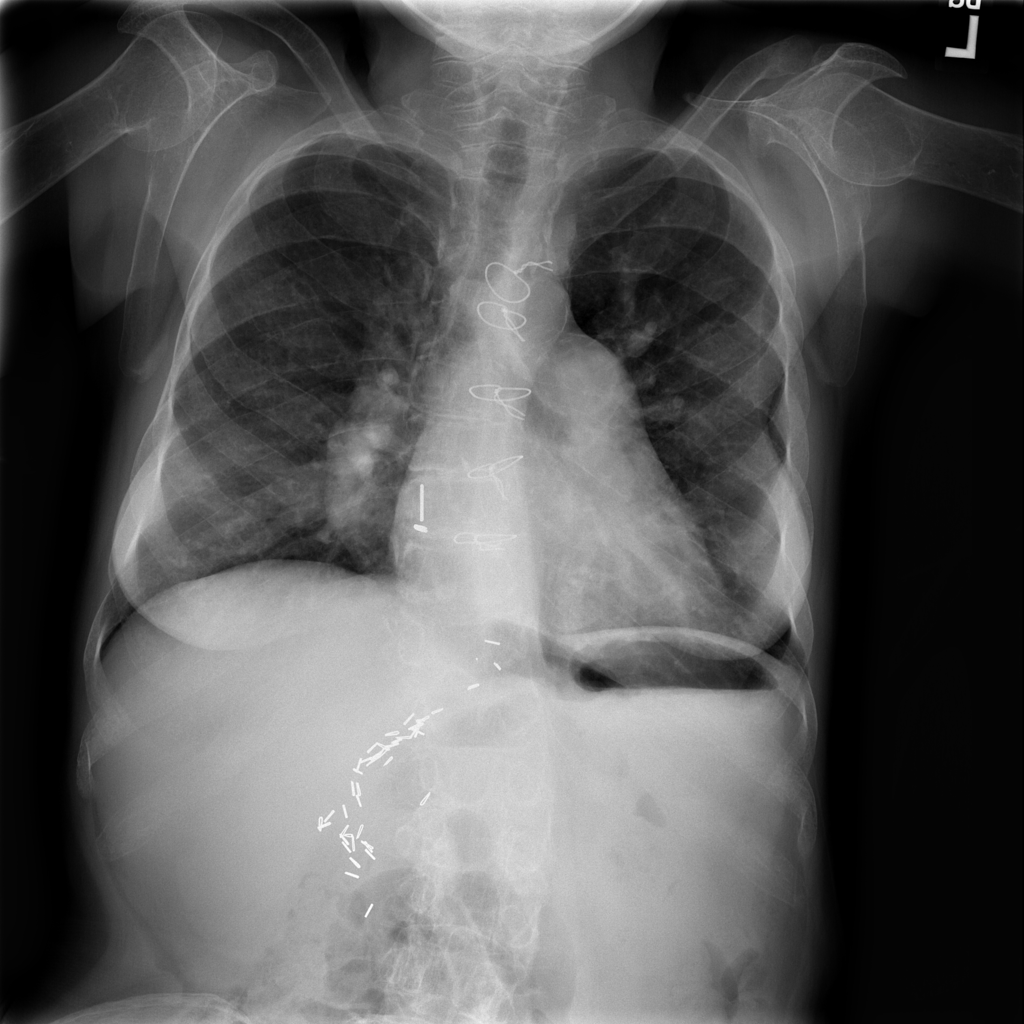

PAT-A5F7 · IMG-002Cardiomegaly

PAT-A5F7 · IMG-002

PA